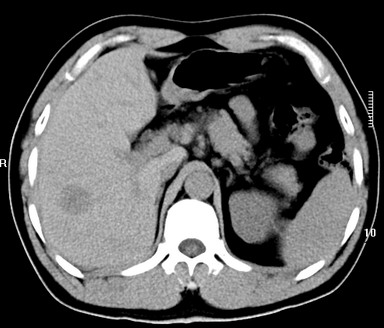

标题: CT19720:肝右叶血管瘤。肝左叶内侧段病灶考虑什么? [打印本页]

标题: CT19720:肝右叶血管瘤。肝左叶内侧段病灶考虑什么?

男,48岁,肝区不适月余,伴隐痛。

支持右叶血管瘤,左叶病灶考虑肝腺瘤。

1)不排除肝左叶肝癌。2)肝右叶血管瘤。

肝左叶炎性病变,肝癌待排。2)肝右叶血管瘤。

1.肝右叶血管瘤;2.肝左叶炎性假瘤?肝癌?建议穿刺活检.

右叶病灶典型,左叶病变慢性炎块

1、肝右叶血管瘤(典型)。

2、肝左叶病灶,强化不明显,疑炎性假瘤,建议结合临床并密切随访。

1、肝左叶炎性病变,肝癌待排。

2、肝右叶血管瘤。

肝左叶脓肿,肝癌待排。2)肝右叶血管瘤